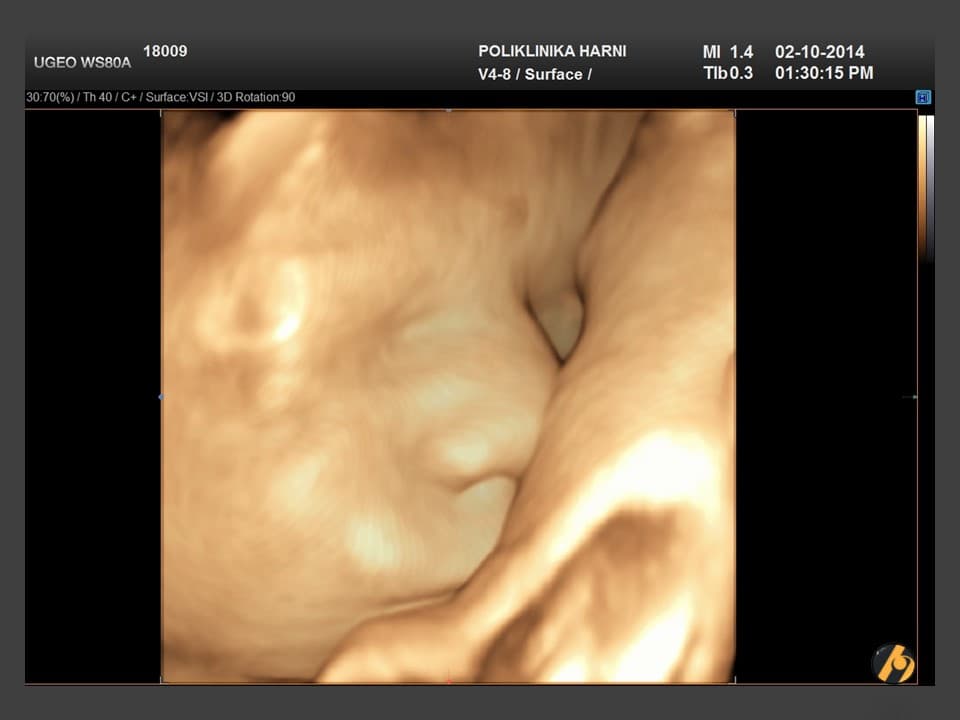

Premda je svijet Vaše bebe ograničen na unutrašnjost maternice, ona će se ponašati baš kao i svako novorođenče, osim što naravno neće plakati.

Sigurno ste prepoznali da Vaša beba ima svoj vlastiti ritam budnosti i spavanja, koji se gotovo uvijek razlikuju od onoga što upravo vi činite. Kada je budna, beba će oponašati ritmične pokrete disanja, gutati plodnu vodu, a može i štucati. Pokreće se, sluša, osjeća, možda i raspoznaje mutne obrise, ali prije svega razvitkom moždanih stanica i veza između njih omogućeno joj je da uči. Beba će puno spavati, njezine oči se pri tome jako pomiču, te stoga pretpostavljamo da može imati i živopisne snove.